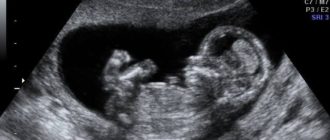

Узи 12-13 недель размер IVжелудочка нормы

Нормы УЗИ и их расшифровка в 12 недель беременности Ультразвуковое исследование на 12-й неделе

Узи 13 недель

Как делают УЗИ на 13-й неделе беременности и как выглядит ребенок: подготовка и расшифровка